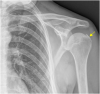

The rotator cuff is a group of four muscles and tendons surrounding the shoulder joint providing it strength and stability. The rotator cuff consists of the subscapularis, supraspinatus, infraspinatus and teres minor. Many shoulder complaints are caused by rotator cuff pathology such as impingement syndrome, tendon tears and other diseases e.g. calcific tendonitis. Diagnosis starts with clinical history and physical examination, after which imaging is often used to help confirm clinical findings depending on the differential diagnosis. The aim of the article is to review the frequently used imaging modalities to assess the rotator cuff and cuff-related disease, specifically focusing on radiography, ultrasonography and magnetic resonance imaging. This article will outline the advantages and disadvantages for each modality and illustrate typical radiological findings of common rotator cuff pathologies.